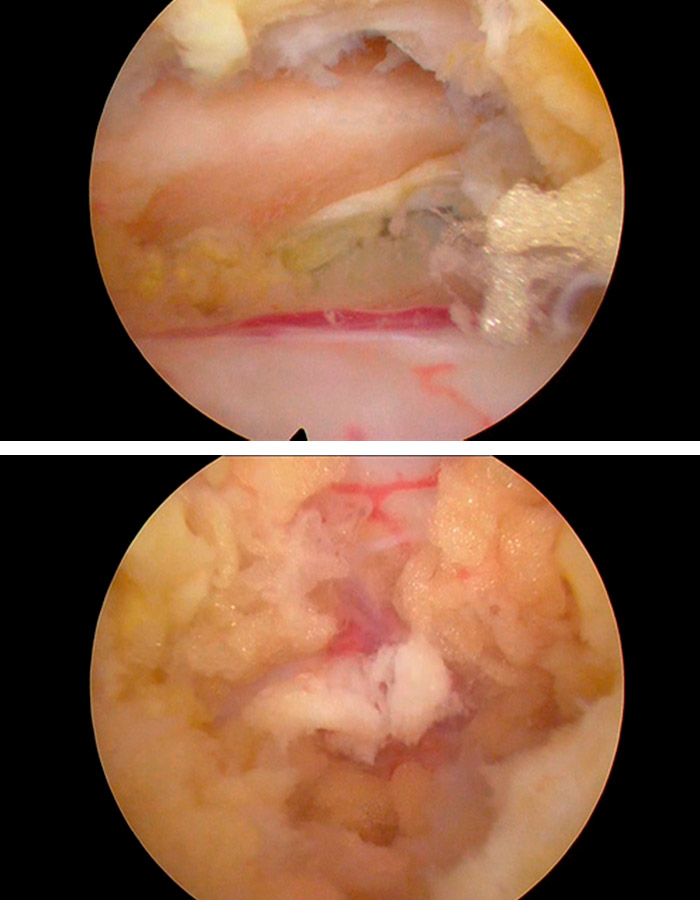

Vision endoscopia del canal cervical

Comenzamos la operación realizando un abordaje interlaminar posterior con una aguja guía que nos ayuda a acceder al ligamento amarillo de forma bilateral.

Una vez hemos ubicado la zona en la que vamos a trabajar se realizan hemilaminectomías superiores también bilateralmente. Este proceso debemos hacerlo hasta haber comprobado la adeucada liberaicón del canal y de las estructuras neurológicas que antes estaban comprometidas.